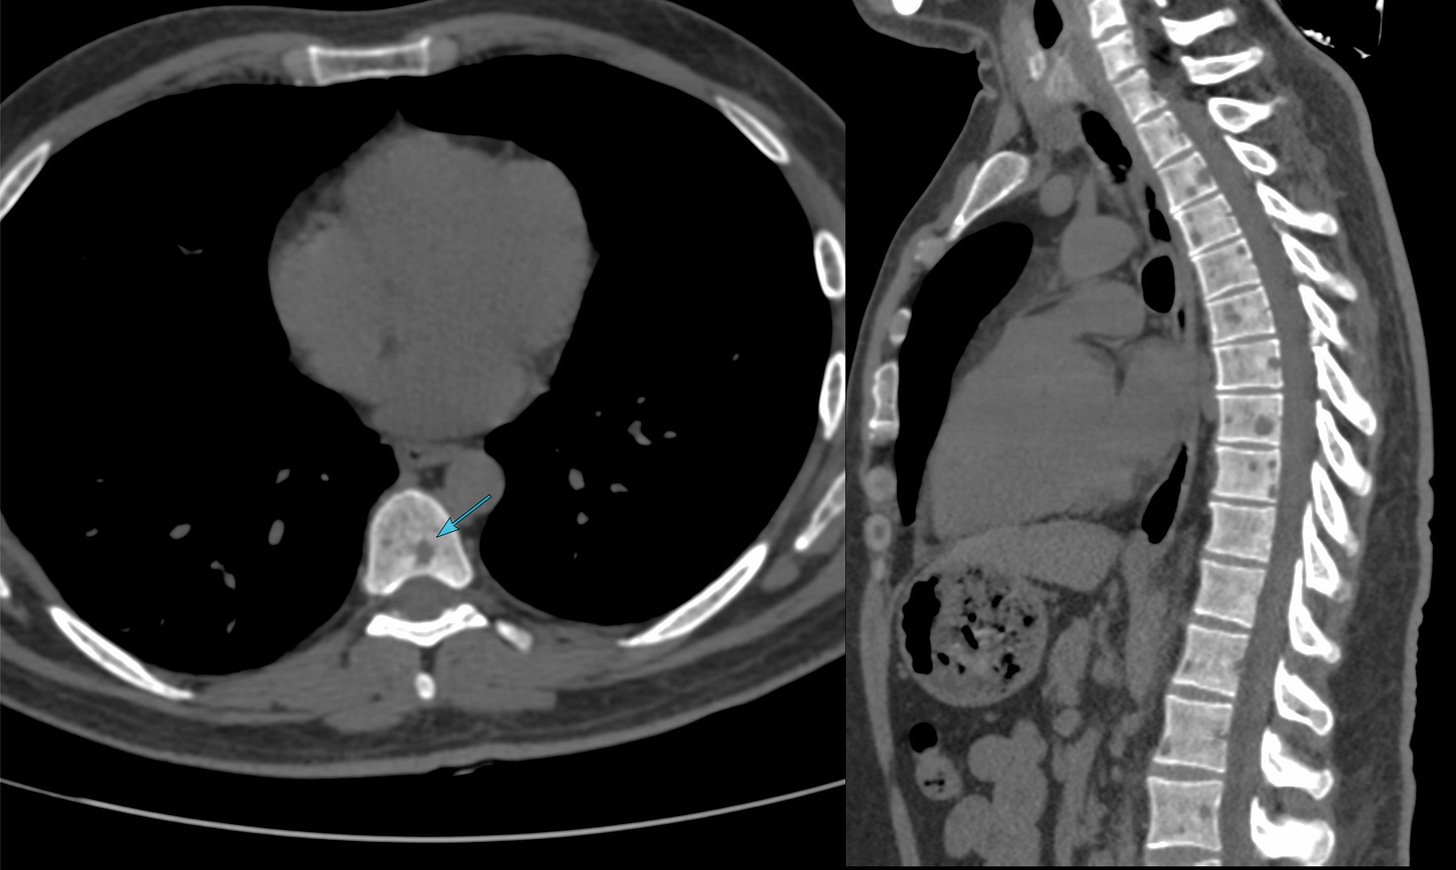

The initial chest CT showed multiple vertebral osteolytic lesions.

These were new compared to a CT scan done 7 months prior. No MRI was done.